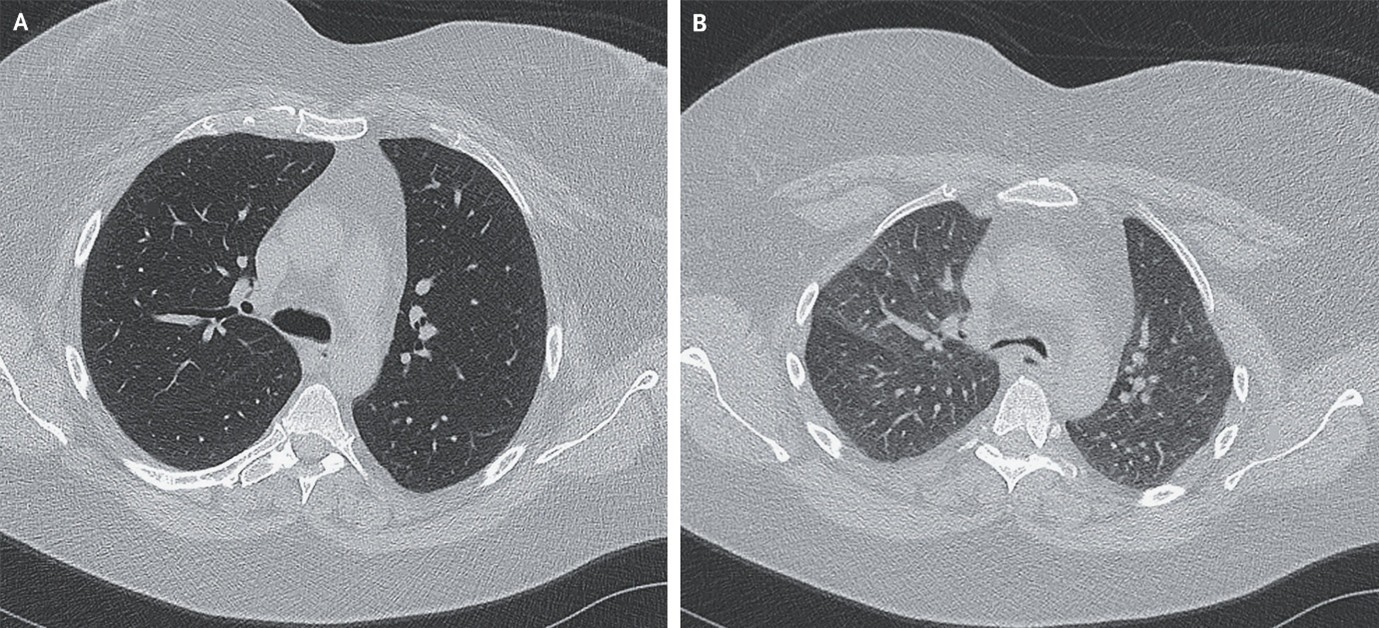

(8). Pulmonary Mucormycosis

Jonas Lötscher, Published February 11, 2026, N Engl J Med 2026;394:699,DOI: 10.1056/NEJMicm2511883, VOL. 394 NO. 7

Abstract

A 49-year-old man with acute myeloid leukemia was evaluated for prolonged neutropenic fever. On examination, there were crackles at the lung bases. CT of the chest revealed a reversed halo sign.